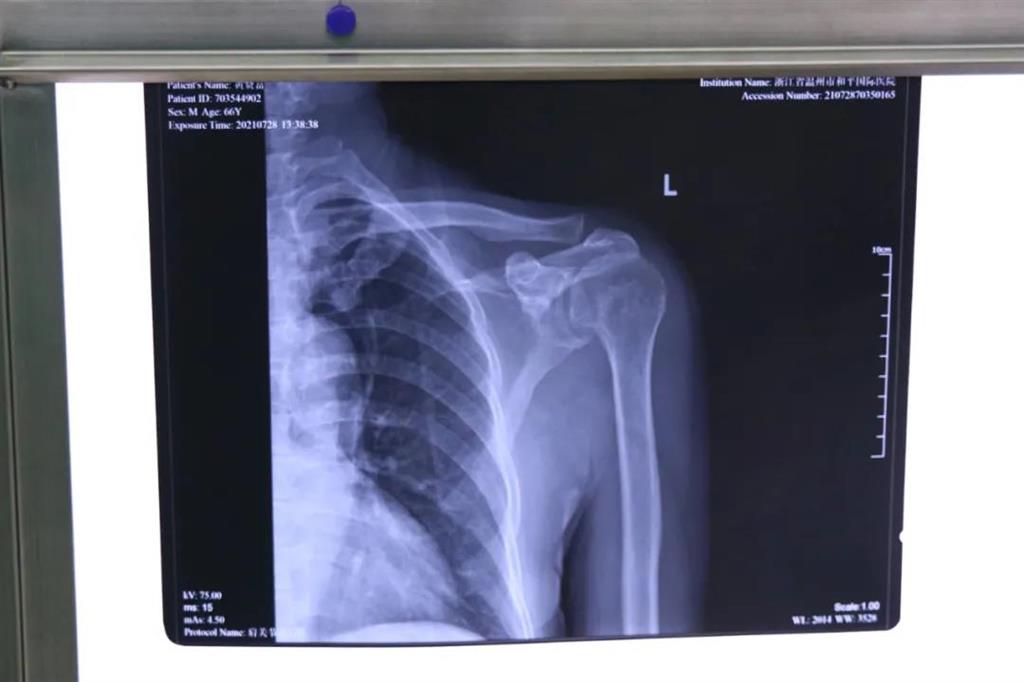

在和平國(guó)際醫(yī)院關(guān)節(jié)鏡微創(chuàng)團(tuán)隊(duì)的協(xié)作下,手術(shù)順利,成功用微創(chuàng)肩關(guān)節(jié)鏡進(jìn)行肩袖修補(bǔ)術(shù)。術(shù)中、術(shù)后患者幾無(wú)出血,且手術(shù)切口小,美觀,患者左肩部疼痛得到明顯緩解。

其中運(yùn)動(dòng)醫(yī)學(xué)四肢創(chuàng)傷科的關(guān)節(jié)鏡微創(chuàng)團(tuán)隊(duì)更是技術(shù)雄厚,團(tuán)隊(duì)成員由上海六院危主任、溫州中心醫(yī)院施主任、溫州和平國(guó)際醫(yī)院副院長(zhǎng)周健醫(yī)師等知名骨科醫(yī)生強(qiáng)強(qiáng)聯(lián)合,為廣大的患者帶來(lái)優(yōu)質(zhì)、高效的骨科診療服務(wù)。